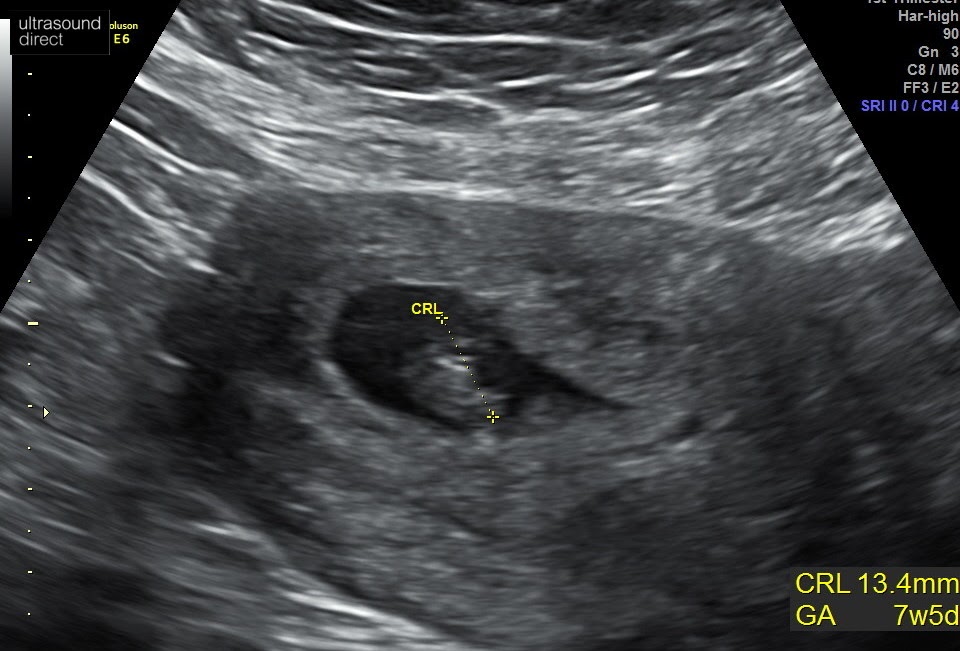

Then this happened..

WOWOWOWOWOWOWOWOWOWOW

I mean how did this happen? Well we all know how.. but I mean we weren’t trying and I didn’t even think this was why I was feeling so rough all of the time.

But what a life saver.